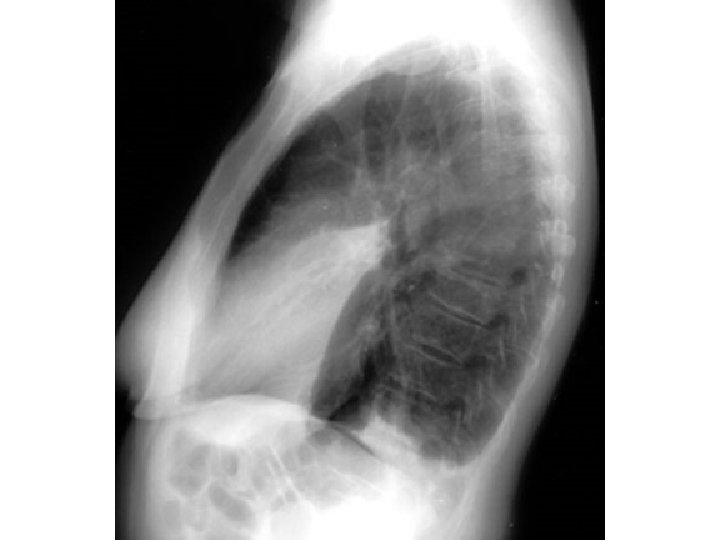

Case 7